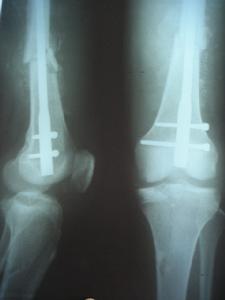

收治病人43例,男27例,女16例,年齡22歲~58歲,平均34.5歲。左20例,右23例。車禍致傷19例,墜落傷4例。按(AO/ASIF)標準分類。A18例、A216例、A36例、B14例、C15例、C23例、C31例。43例隨機分為兩組,兩組性別、年齡、骨折類型無顯著性差異,分別採用動力髁螺釘(DCS)內固定(A組24例)和髁鋼板內固定治療(B組19例)。

A組:24例採用切開復位DCS內固定。連續硬膜外麻醉,股外側縱切口,切開皮膚及闊筋膜,分離股外側肌,切開骨膜並行骨膜下剝離,充分顯露骨折端。先將髁部骨折復位,使關節面達到解剖復位,用克氏針或持骨鉗將骨折塊固定,再將髁與乾復位,取髁外側股骨長軸線上距遠端關節面2cm為進針點,用95°髁導向器定位,由外向內平行於前髁關節面打入導針,X線證實位置良好,用DCS鋼板模擬測試後,三聯鑽鑽骨,測深、攻紋,擰入動力髁釘、套入鋼板,用持骨鉗將鋼板夾在股骨幹上,分別擰入其它皮質骨螺釘,最後擰緊加壓螺釘尾。有骨缺損者常規植骨。B組19例採用髁鋼板內固定。手術方法基本同前,不同處是:

①股骨髁外側需廣泛顯露;

②髁部用多枚松質骨螺釘固定。

術後不用外固定,傷口內放置引流,48h~72h拔除。拔引流後即開始股四頭肌鍛練,A組同時開始CPM功能鍛練,B組4W開始CPM功能鍛練。4W開始扶雙拐不負重下地活動,10W~12W開始練習負重行走。

結果

所有病例進行了隨防無感染髮生,全部骨性癒合骨折癒合時間為8W~24W,平均12W,A組膝關節功能:平均伸0°∥屈130°無膝內外翻,B組:伸0°∥屈120°8例合併膝內翻。討論